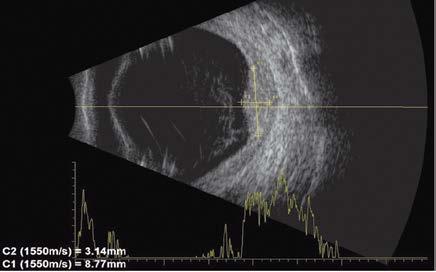

A la exploración, se encuentra agudeza visual de ojo derecho 20/40, ojo izquierdo percepción de luz, con presión intraocular de ambos ojos de 12 mmHg (tonómetro de Goldmann), segmento anterior sin alteraciones de importancia, pseudofaco y fondo de ojo izquierdo con una hemorragia vítrea grado IV. Se solicita ecografía de ojo izquierdo la cual mostró una hemorragia vítrea con desprendimiento de retina sero-hemático con elevación coroidea de 8.77 mm x 3.14 mm, localizada en cuadrante temporal inferior, con una reflectividad interna baja (33%) (Imagen-1).

Imagen 1. Ecografía de ojo izquierdo: